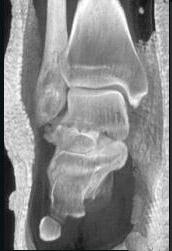

问题 男,28岁,从高处坠落后双足剧痛一月余,请结合影像学检查,选出最可能的诊断 ( )

选项 A、舟状骨骨折 B、楔骨骨折 C、骰骨骨折 D、距骨骨折 E、跟骨骨折

答案 D